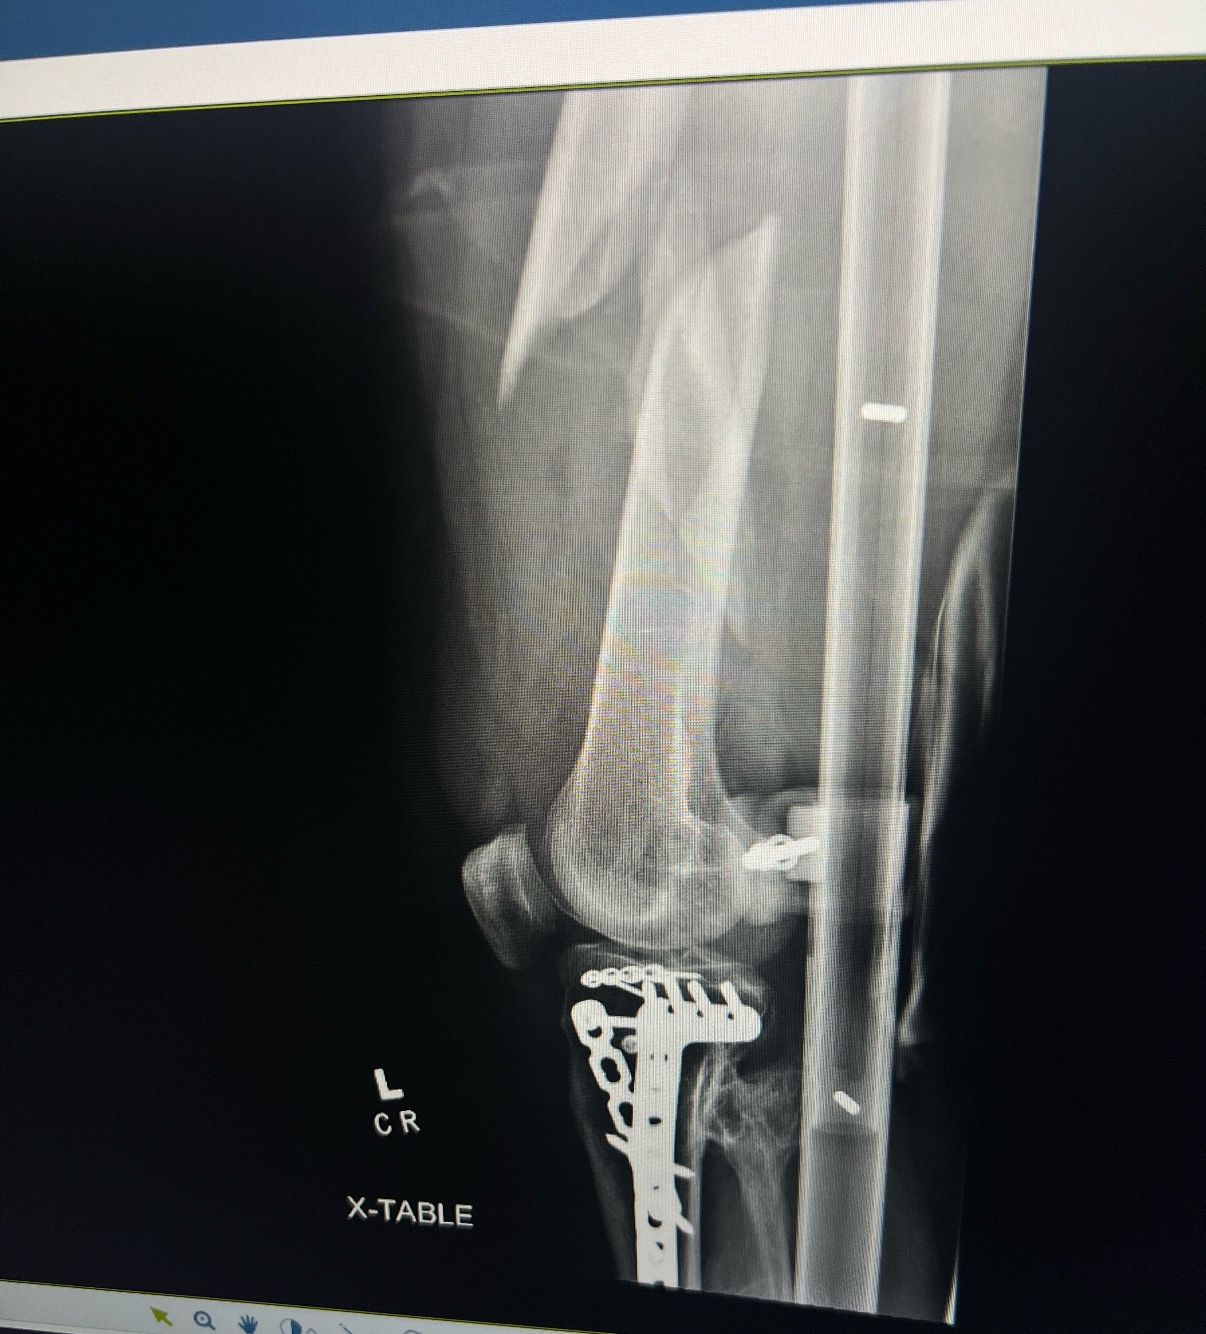

Her insurance is also claiming her femur break was not an emergency, therefore, trying not to cover it and put it towards her deductible. With the new surgery approaching (because she technically hasn’t met the deductible due to them offsetting this cost onto her-she is going to try to fight it)she will now have to pay out-of-pocket upfront a portion of this surgery cost.

While shes since returned to work, it’s only been part-time as shes still recovering from a broken femur. Unfortunately, she now needs an additional surgery on her hand to insert a pin and undergo bone grafting. She will be in a hard cast for at least two weeks and unable to work during that time.